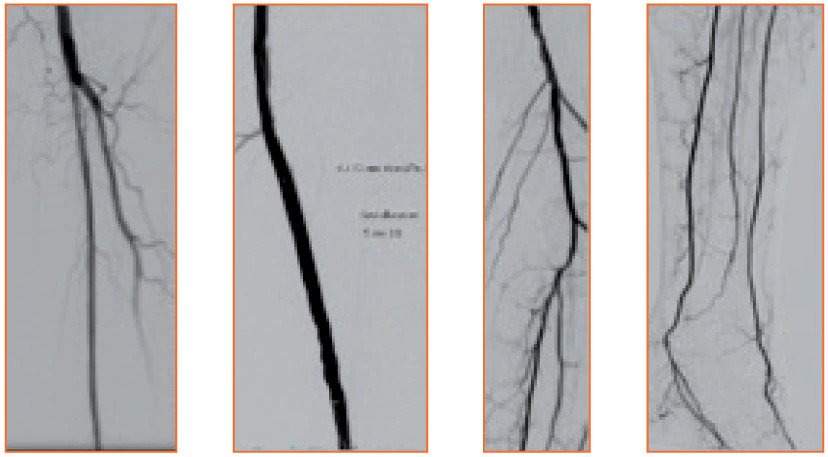

In-Stent Restenosis Cases

Case 1 Case 1

Case 1

Case 2 Case 2

Case 2

Case 3 Case 3

Case 3

<h3>Dr. Aaron Frodsham, MD.&nbsp; Salt Lake City, UT, USA</h3>

Dr. Aaron Frodsham, MD.  Salt Lake City, UT, USA

<h3>Dr. Aaron Frodsham, MD. Salt Lake City, UT, USA</h3>

<h3>Dr. John Park, MD. Omaha, NE, USA</h3>

Dr. John Park, MD. Omaha, NE, USA